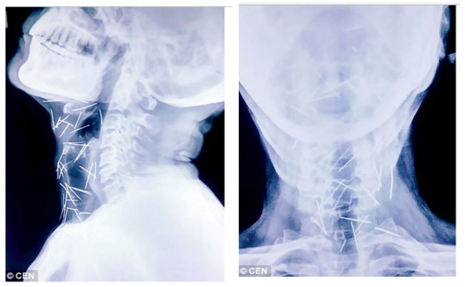

Vietbf.com - Sau khi đau chân đi khám đưa người đàn ông vào bệnh viện để phẫu thuật ngón chân cái, thì bác sĩ phát hiện trong chân ông có nhiều cây kim, khi tiếp tục kiểm tra, các bác sĩ phát hiện có tới 75 cây kim trong cơ thể, có 40 cây nằm trong cổ họng, 25 cây ở chân và 2 cây ở cánh tay, người thân của ông ta cảm thấy vô cùng sợ hãi.

Thế nhưng, trong quá trình chụp X-quang để kiểm tra tổng thể, các bác sĩ đã vô cùng sửng sốt khi phát hiện có đến 75 chiếc kim đâm trên khắp người bệnh nhân, từ cổ, vai cho đến chân.

Ảnh chụp X-quang cho thấy kim nằm trong cổ bệnh nhân. Ảnh: DAILY MAIL

Cho đến nay, vẫn chưa một bệnh viện nào trong số những nơi ông Meena đến thăm khám đồng ý rút kim ra khỏi cơ thể cho ông ta. Trong số 75 chiếc kim nói trên, có 40 chiếc đâm quanh khu vực họng, 25 chiếc đâm ở chân, còn lại là ở những chỗ khác.